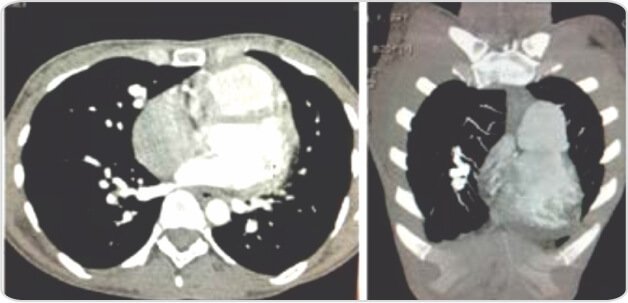

عند الفحص، كان المريض مستقرًا من الناحية الديناميكية الدموية بمعدل نبض قدره 90 في الدقيقة، وضغط دم يبلغ 140/90 ملم زئبق وتشبع بالأكسجين بنسبة 90٪ على مقياس التأكسج النبضي الذي يُمسك بالإصبع. أظهر فحص تجويف الفم توسع الشعيرات الدموية عن طريق الفم، وعند سماع الثدي الأيمن ومنطقة داخل الكتف اليمنى، تم سماع لغط خافت. كانت فحوصات البطن والعصبية طبيعية. وأظهرت التحقيقات أن الهيموجلوبين يبلغ 12.1 جم/ديسيلتر، وحجم الخلايا المعبأة 56%؛ عدد خلايا الدم البيضاء 9,400 لكل ملم مكعب (متعددة الأشكال 79%، خلايا ليمفاوية 17%، حمضات 2%، قاعدة 2%). وكانت المعلمات البيوكيميائية الأخرى ضمن الحدود الطبيعية. أظهر مخطط كهربية القلب (ECG) عدم انتظام دقات القلب الجيبي مع انحراف المحور الأيمن وموجة R في V1. نظرًا لأن المريض كان يعاني من عدة نوبات من الرعاف والاشتباه في حدوث انسداد رئوي، فقد خضع المريض لتصوير مقطعي محوسب للصدر وتصوير الأوعية الدموية الرئوية. كشف تصوير الأوعية الرئوية عن تمدد الأوعية الدموية الكاذب مع ناسور شرياني وريدي ناشئ عن فروع الشرايين الرئوية اليمنى.

التشوه الشرياني الوريدي الرئوي